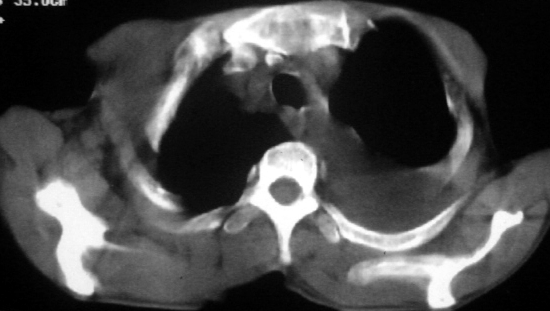

男,54岁,咳嗽,气喘半年,胸痛一月.

血性胸水

左侧胸腔积液 斜裂积液 心包积液 左肺不张 考虑左肺ca并胸膜心包转移。

支持左肺下叶中心型肺癌(累及舌叶)伴阻塞性肺炎、膨胀不全、胸腔积液、心包少量积液。

考虑左肺下叶中央型肺癌伴阻塞性肺炎及肺不张,纵隔受累可能,胸膜转移。

左肺下叶中心型肺癌,伴阻塞性肺炎、左胸腔积液、心包少量积液。

1.左肺下叶中心性肺癌伴阻塞性肺炎,肺不张.

2.左侧胸腔积液,心包积液